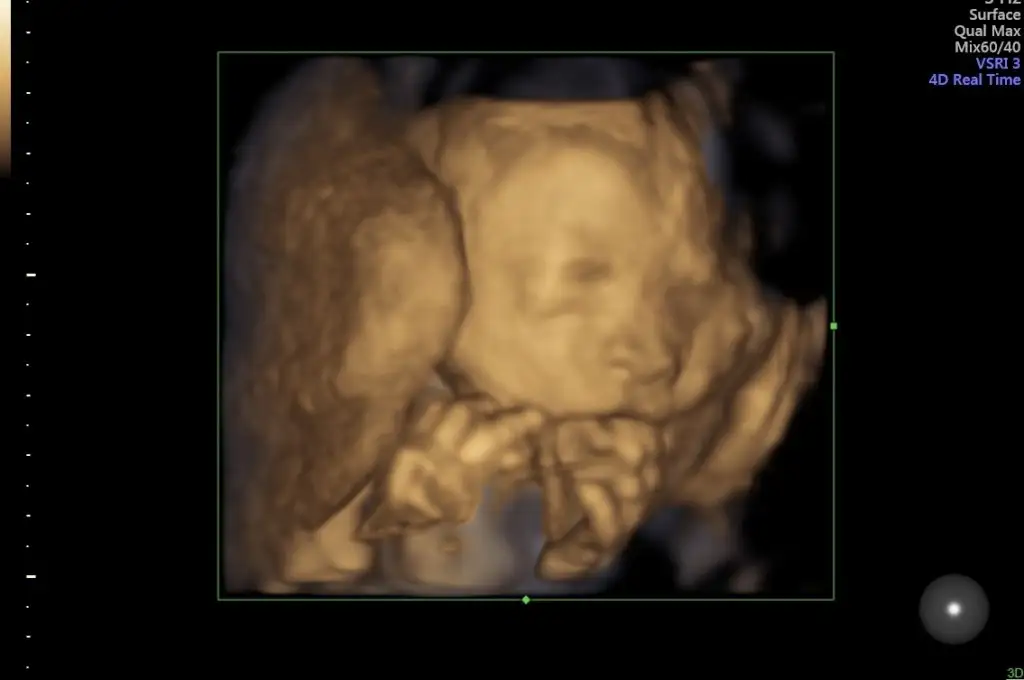

Aç mi gitmiştin ben hep biseyler atistirip gidiyorum her gitmemde yuzu böyle 🙈

Kahvalti ettim bir de üstüne çikolata yedim hadi belki işe yarar diye😂 hastaneye gittiğimizi mi anlıyornmu nedir hep böyle uyuyor😅 eve geldiğimizde tekmelemeye baslıyor dogumda görcez artık yüzünü😂

Detaylı ultrasondan fotoğraflarımız var ama üzerinden 2 ay gecti değişmiştir diye düşünüyorum😌